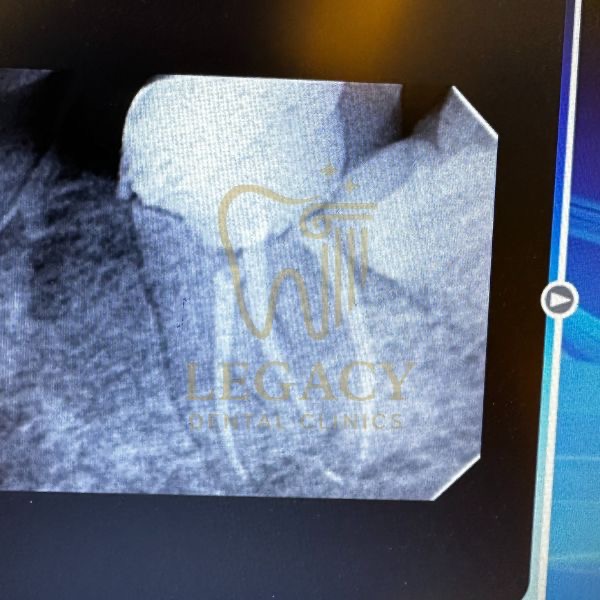

حالة زراعة فورية لسن أمامي - د.عمر نافوخ